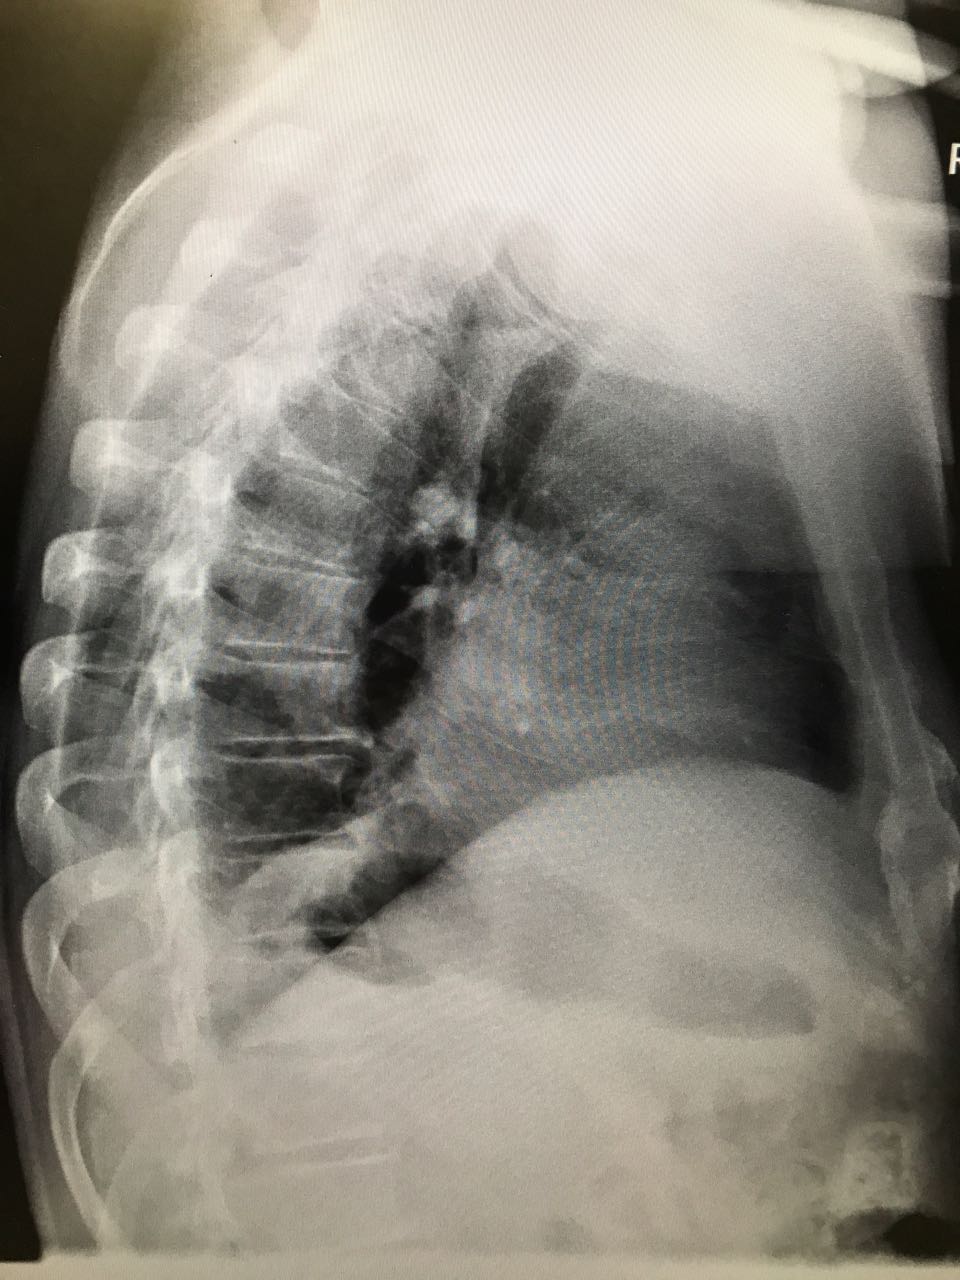

На рентгене гиповентиляция - признак центрального рака

Обсуждалось в Госпитале Ослабленных Сердец

Вложения:

1.jpg

1.jpg [ 153.7 KiB | Просмотров: 59333 ]

2.jpg

2.jpg [ 116.83 KiB | Просмотров: 59333 ]

IMG_7902-.jpg

IMG_7902-.jpg [ 380.61 KiB | Просмотров: 59333 ]

Rotation of IMG_7904-.jpg

Rotation of IMG_7904-.jpg [ 467.04 KiB | Просмотров: 59333 ]